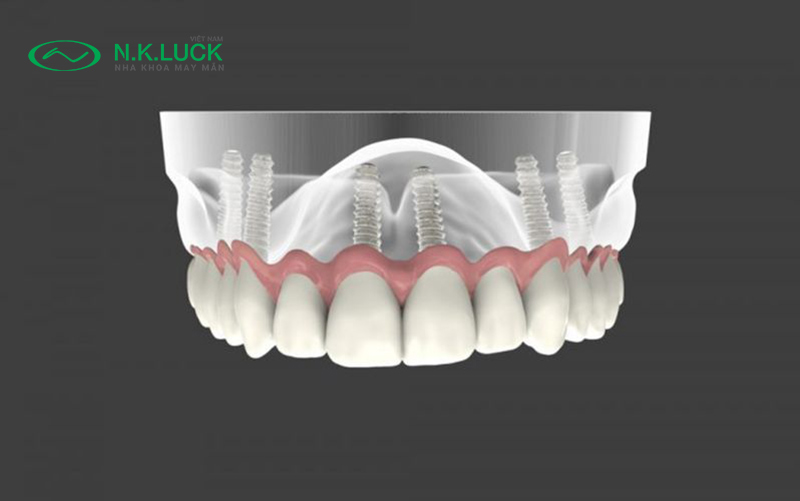

Răng sứ Vita Zirconia là sản phẩm được ra đời bởi ứng dụng của nha khoa kỹ thuật số – CAD/CAM (Computer Aided Design/Computer Aided Manufacturing). Đây là công nghệ thiết kế – chế tác răng sứ nguyên khối thế hệ mới, được thực hiện hoàn toàn tự động bằng máy. Nhờ đó, răng sứ thành phẩm có độ chính xác tuyệt đối và đặc biệt là thời gian thiết kế nhanh chóng hơn cả so với kỹ thuật chế tạo phục hình răng sứ truyền thống ở labo, góp phần đơn giản hóa quy trình làm việc của nha sĩ.

Công nghệ chế tác răng sứ CAD/CAM đặc biệt nổi bật bởi kỹ thuật Scan. Kỹ thuật này giúp răng được sửa soạn và tương thích chính xác với xương hàm, từ đó tạo nên tương quan với khớp cắn, sau cùng là truyền tải vào máy tính, mang lại kết quả phục hình răng sứ chính xác, hoàn hảo.